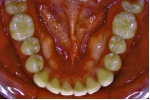

初診時

|